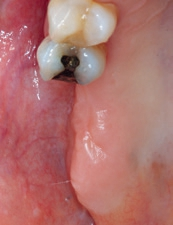

Nach weiteren 3 Monaten Einheilzeit wurde zur Freilegung der Implantate ein nach vestibulär versetzter Spaltlappen präpariert. Im krestalen Bereich wurde das Periost perforiert sowie die Deckschrauben der Implantate entfernt und mit einem Gingivaformer (Wide Body, Camlog) versehen (Abb. 11). Der apikale Verschiebelappen wurde apikal mit dem Periost vernäht (Seralon 6/0, Serag-Wiessner). Danach wurde die Patientin zu ihrem Hauszahnarzt (Dr. Marc Mauch, Stuttgart) für die prothetische Weiterbehandlung zurücküberwiesen (Abb. 12). Die Suprakonstruktion konnte aufgrund des stabilen Implantatlagers ohne Verblockung der beiden Einzelkronen erfolgen (Zahntechnik, Waiblinger Dentallabor, Waiblingen) (Abb. 13a und b). Im Rahmen der Implantatnachsorge zeigten sich bei der Patientin stabile periimplantäre Weich- und Hartgewebsverhältnisse. Die Röntgenkontrolle 20 Monate nach prothetischer Versorgung zeigte ein im Vergleich zur Röntgenkontrolle nach 6 Monaten ein stabiles vertikales Knochenniveau (Abb. 14).